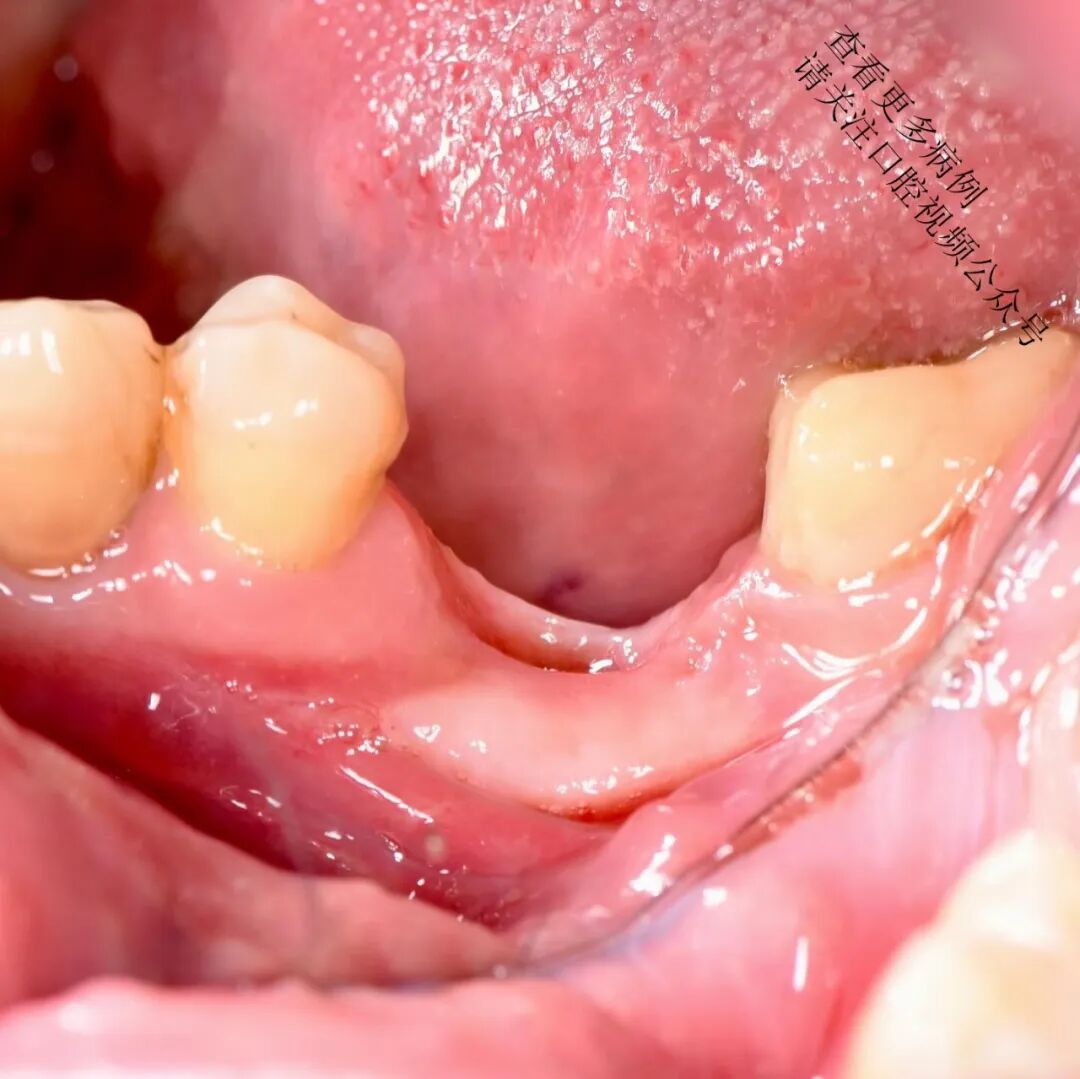

从腭部获取结缔组织移植材料(CTG / ССТ)

使用不可吸收缝线(如Prolene 6/0)将移植片紧密固定于骨膜上